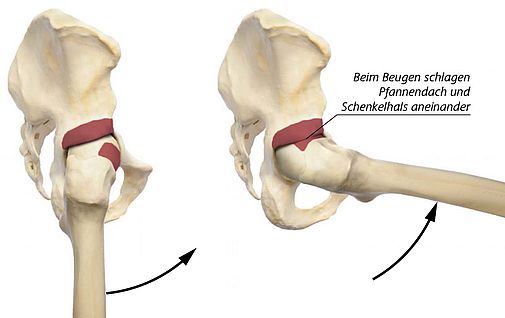

Da das Hüftgelenk durch die enge knöcherne und die kräftige Weichteilführung keinen Spielraum für Ausweichbewegungen bietet, verursachen schon die geringsten Passungenauigkeiten der Gelenkpartner einen mechanischen Konflikt. Diese Formstörung kann entweder seitens der Pfanne und/oder des Hüftkopf-Schenkelhalses auftreten.

Bei etwa 15% aller Europäer liegt eine Abweichung von der Norm am Schenkelhals und/oder an der Hüftpfanne vor. Bei einem „ZU VIEL“ der Pfanne wird der Hüftkopf von der knöchernen Umfassung der Pfanne in die Zange genommen.

Dieses Zangenphänomen wird als PINCER Impingement (engl. PINCER = Beißzange) bezeichnet.

Bei einer unzureichenden Taillierung des Hüftkopf-Schenkelhals-Übergangs kommt es bei der Beugung des Gelenks zu einem Einpressen des entrundeten, nicht mehr kugelförmigen Hüftkopfes in die kugelförmige Hüftpfanne. Dieser Vorgang gleicht dem Prinzip einer mechanischen Nockenwelle und wird deshalb als CAM Impingement (engl. CAM = Nockenwelle) bezeichnet.

Häufig liegen beide Formstörungen vor, was das Problem noch verstärkt, und so können schon geringe Abweichungen von der Norm auf Dauer das Gelenk schädigen.

Das bedeutet, dass sich das Hüftgelenk im Laufe der Zeit selbst zerstört. Genau hier setzt unsere Therapie an.